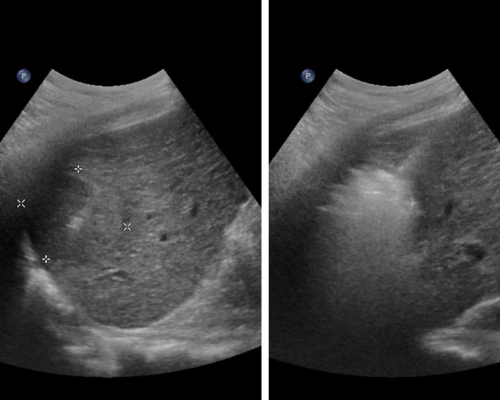

Image-guided liver cancer ablation is a non-surgical treatment used to destroy selected liver tumours using controlled thermal energy, delivered precisely under ultrasound or CT guidance.

Liver cancer ablation is a minimally invasive, image-guided treatment in which a thin needle is placed into the tumour under ultrasound or CT guidance. Controlled heat (radiofrequency or microwave) is used to destroy cancer cells while preserving surrounding healthy liver tissue, often avoiding surgery.